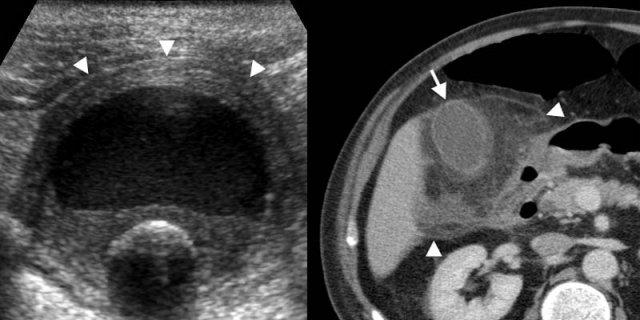

Trường hợp bên trái là bệnh nhân bị xơ gan.

Dày thành túi mật thứ phát có thể là do tăng áp lực tĩnh mạch cửa và giảm áp lực thẩm thấu nội mạch.

Bên trái là nam giới 75 tuổi bị viêm gan do thuốc.

Hình siêu âm cắt dọc của túi mật không căng giãn cho thấy dày thành lan tỏa (mũi tên), và sỏi túi mật tình cờ phát hiện có thể gây nhầm lẫn trong chẩn đoán.